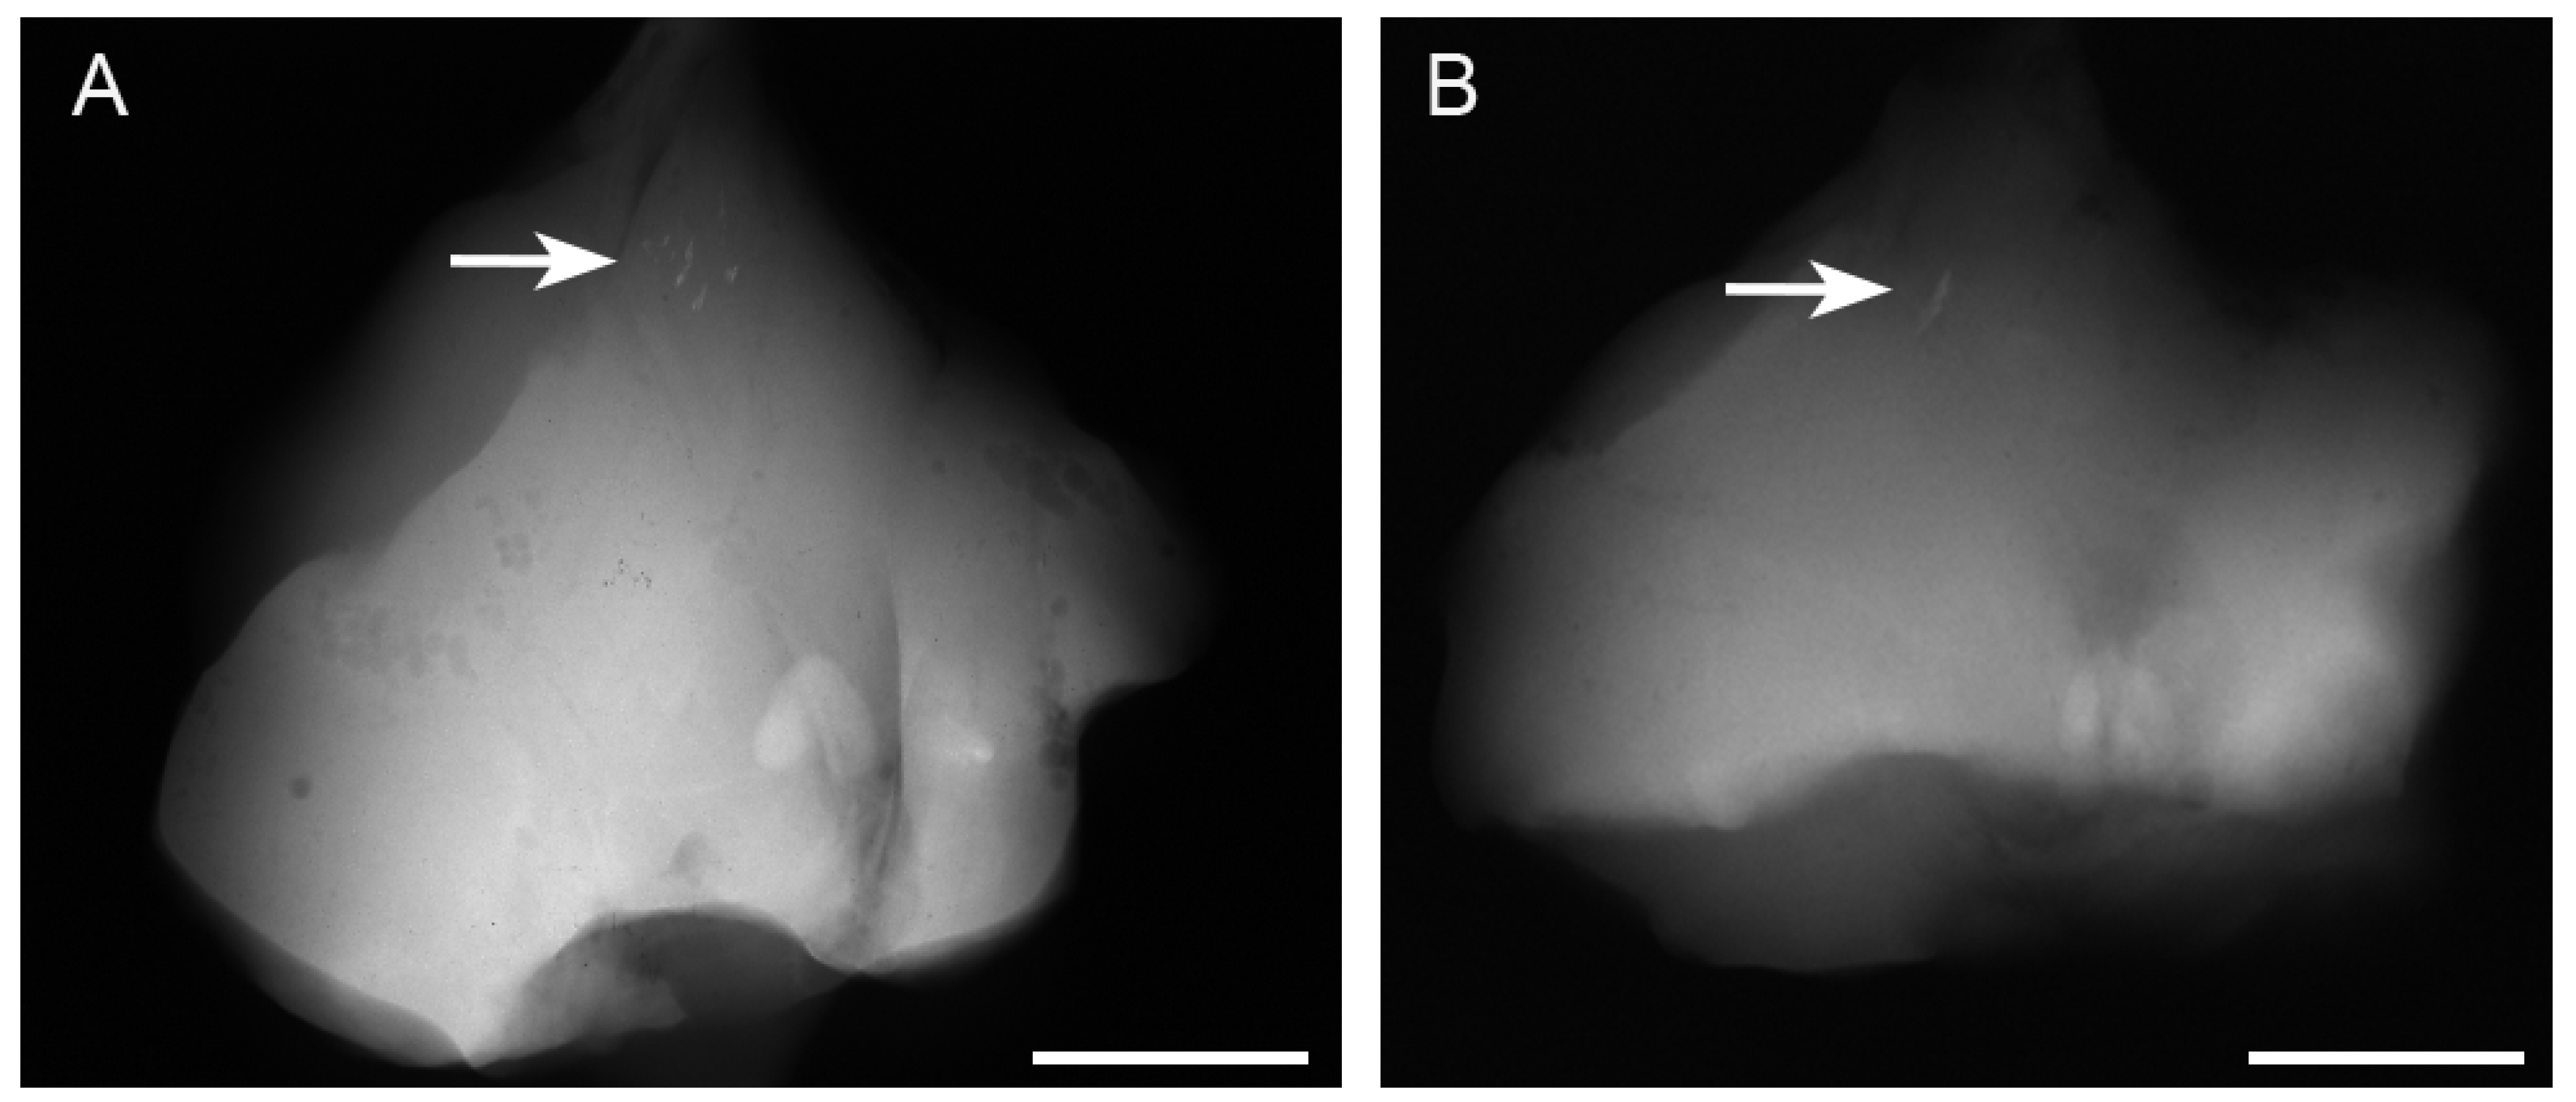

3.1. Radiographic Findings